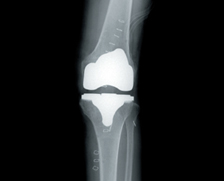

• 사전 인공관절 선택과 정확한 인공관절 삽입

정확한 수술계획만큼 중요한 것은 인공관절의 선택과 삽입입니다.

의사는 로봇을 이용해 환자의 관절에 맞는 인공관절을 선택하고 정확하게 삽입합니다.